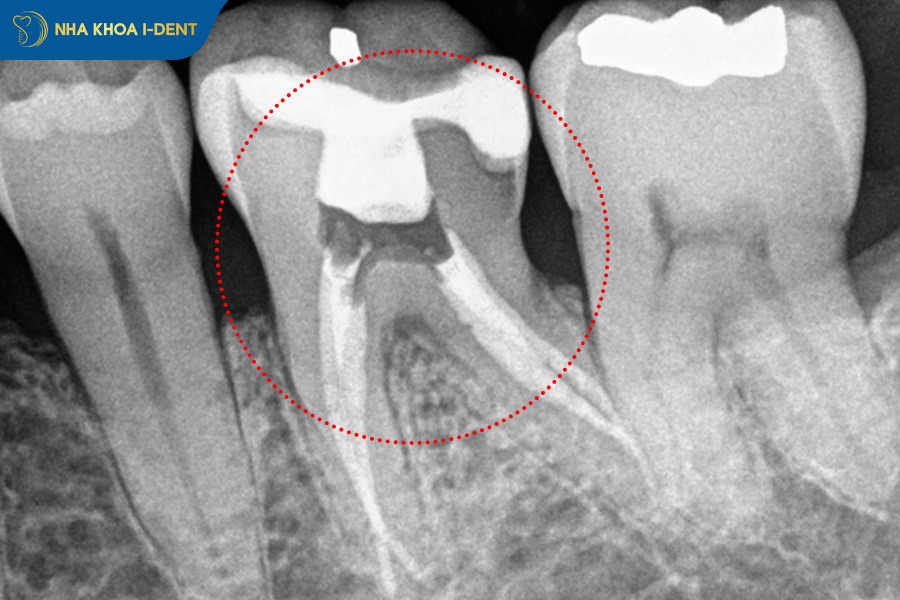

3.3 Tình trạng răng đã lấy tủy

Trước khi niềng răng trên răng bọc sứ, bác sĩ cần đánh giá chất lượng răng thật bên dưới xem răng đã lấy tủy hay chưa. Vì răng đã lấy tủy sẽ mất đi một phần cấu trúc và độ rắn chắc tự nhiên nên khả năng chịu lực kéo từ mắc cài hoặc khay niềng sẽ giảm. Nếu nhiều răng trong hàm đã lấy tủy và đồng thời bị mài nhiều để bọc sứ thì quá trình niềng sẽ gặp khó khăn và khó kiểm soát lực nên nguy cơ răng sứ bật ra hoặc hư hỏng là rất cao.

Ngoài ra, việc đánh giá tình trạng răng trước niềng cũng bác sĩ lập kế hoạch điều chỉnh lực phù hợp, xác định răng nào có thể dịch chuyển an toàn và răng nào cần bảo vệ đặc biệt. Đây là bước quan trọng để đảm bảo quá trình niềng răng diễn ra hiệu quả mà không gây tổn hại đến mão sứ hoặc cùi răng thật bên trong.

Răng đã lấy tủy sẽ khó có thể niềng răng được.